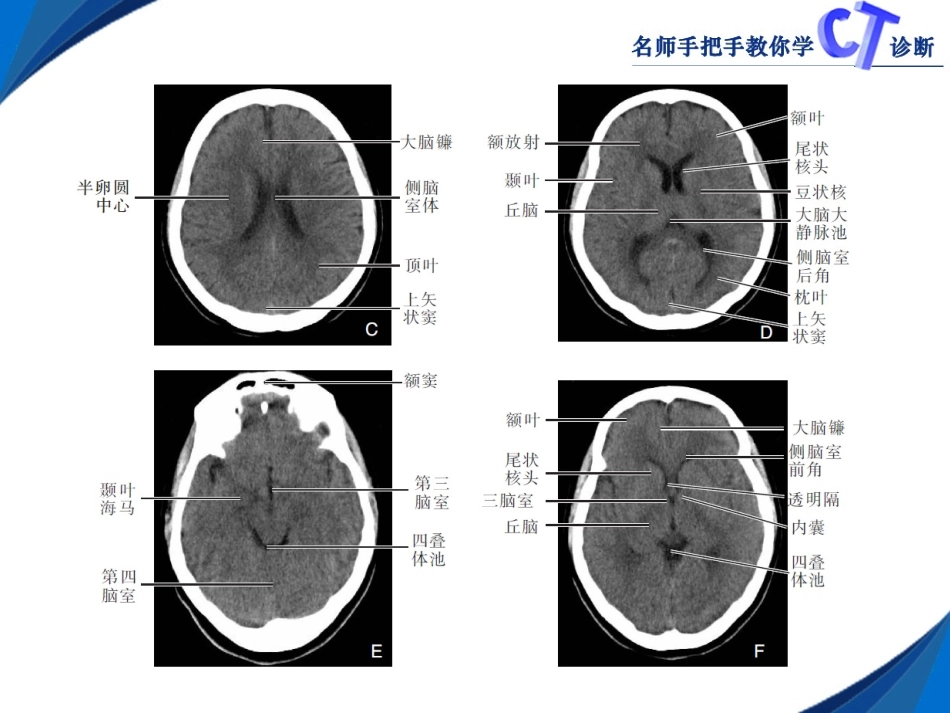

第二章颅脑第一节正常断面CT表现颅脑包括颅盖软组织(头皮)、颅骨、脑实质、脑膜及其间隙。第二节颅脑先天性病变一、Dandy-Walker综合征【典型病例】患者,女,10岁,进行性头颅增大三个月,头部不适就诊。【CT诊断要点】1.第四脑室极度扩大,呈脑脊液密度,在背侧与枕大池形成大量充满脑脊液的复合体。2.颅后窝增大,小脑幕高位;小脑蚓部部分或完全缺如;小脑半球发育不全、变小,并前移;75%合并脑积水。3.可并发其他畸形时,有相应的CT表现。二、脑裂、脑沟和脑回发育畸形【典型病例】1.患者,男,8岁,间断性抽搐半年就诊。2.患者,女,21岁,间断性头疼,智力低下。【CT诊断要点】1.两侧或单侧中央前、后回区大脑表面异常增宽或较窄的裂隙延伸到侧脑室的室管膜下区。2.侧脑室外壁局限性峰状突起,与裂隙相连,裂隙边缘可见密度较高的皮层灰质结构。三、脑膜膨出患者,男,4个月,主因额部肿物来诊。【CT诊断要点】1.颅骨缺损,边缘较完整,多呈弧形。2.膨出的囊腔呈脑脊液密度,膨出后形成疝,包括“疝囊”、“疝颈”。疝囊的边界一般清楚、光滑,囊壁由脑膜组织组成。3.脑室受牵拉而变形、移位或与囊腔相同。4.可并发其他畸形时,有相应的CT表现。四、先天性脑积水【典型病例】患者,男,11个月,头颅增大。【CT诊断要点】1.头颅增大,颅骨变薄,颅缝分离及前、后囟延迟闭合或明显扩大。2.幕上大脑半球区为脑脊液密度。额顶颞叶脑实质残留极少。部分枕叶、基底节及丘脑保存。3.小脑、脑干和第四脑室发育一般正常。大脑镰结构正常。五、胼胝体发育不良【典型病例】1.患者,男,21岁,主因智力低下,癫痫间断发作10余年,近日癫痫发作频繁来诊。2.患者,男,16岁,主因智力低下,间断性癫痫发作就诊。【CT诊断要点】1.双侧侧脑室体部间距增大呈平行分离,侧脑室前角变窄,后角相对扩大,呈八字分离;第三脑室增宽并上移,位于侧脑室体部之间。2.多见于胼胝体嘴部或后部受累,可并有海马旁回及前、后连合完全或部分性缺如或海马联合增大。3.可伴有其他颅内畸形,如脑裂畸形、灰质异位,纵裂内蛛网膜囊肿。六、Chiari畸形【典型病例】患者,女,35岁,无任何症状,随单位体检来诊。【CT诊断要点】1.表现为小脑扁桃体下疝,在椎管上端可见两个软组织影,后方一个呈新月形,为下疝扁桃体,前方为延髓或颈髓上段。2.伴发脊髓空洞症。3.岩骨及斜坡呈扇贝壳样变化,内听道缩短、其内端截断,天幕下蛛网膜下腔受压,枕大池形成不良或缺如。七、灰质异位【典型病例】患者,男,癫痫间断发作20年来诊。【CT诊断要点】1.一般呈板层或团块状,多位于半卵圆中心或侧脑室旁白质内,呈相对稍高密度,与正常灰质密度相等,病变周围无水肿和占位效应;可伴发头小畸形、胼胝体发育不良、小脑发育异常等先天发育畸形。2.增强扫描病变区与正常大脑灰质的强化一致。八、结节性硬化【典型病例】患者,男,15岁,以癫痫间断性癫痫发作15年,伴智力低下,皮脂腺瘤来诊。【CT诊断要点】1.病变常沿室管膜下与侧脑室边缘分布,呈圆形或形态各异、大小不一的结节和钙化,双侧对称分布,钙化率可达90%以上。2.可突入脑室,呈软组织密度,造成侧脑室壁缺损;10%~15%室管膜下结节伴发巨细胞星形细胞瘤和少突胶质细胞瘤,可伴发脑积水。3.可伴发灰质异位。4.突入脑室结节病灶呈中度强化,灰质结节一般不强化,钙化无强化。第三节颅脑创伤一、颅盖骨骨折【典型病例】1.患者,男,35岁,主因脑外伤2天,左耳流血,颅骨多发骨折。2.患者,男,23岁,外伤,皮下肿胀。【CT诊断要点】骨窗图像上可见颅骨全层断裂,个别可见单独的内板骨折,骨折线宽窄不一,边缘锐利、僵直,凹陷骨折全层凹入颅内,压迫脑组织,常伴有帽状腱膜下血肿或骨膜下血肿,颅内常合并硬膜外血肿。二、颅底骨折【典型病例】患者,男,18岁,外伤3小时,右侧外耳道流血伴局部肿胀。【CT诊断要点】经过颅底横断面图像观察清晰可见骨折线的部位、形态和走行,对于细小的颅底骨折应薄层高分辩检查,重点注意脑脊液鼻漏的漏出部位,尤其是筛板、眶顶、蝶窦或额窦、视神经管,有时可见颅内积气。三、脑挫裂伤【典型病例】患者,男,19岁,因车...